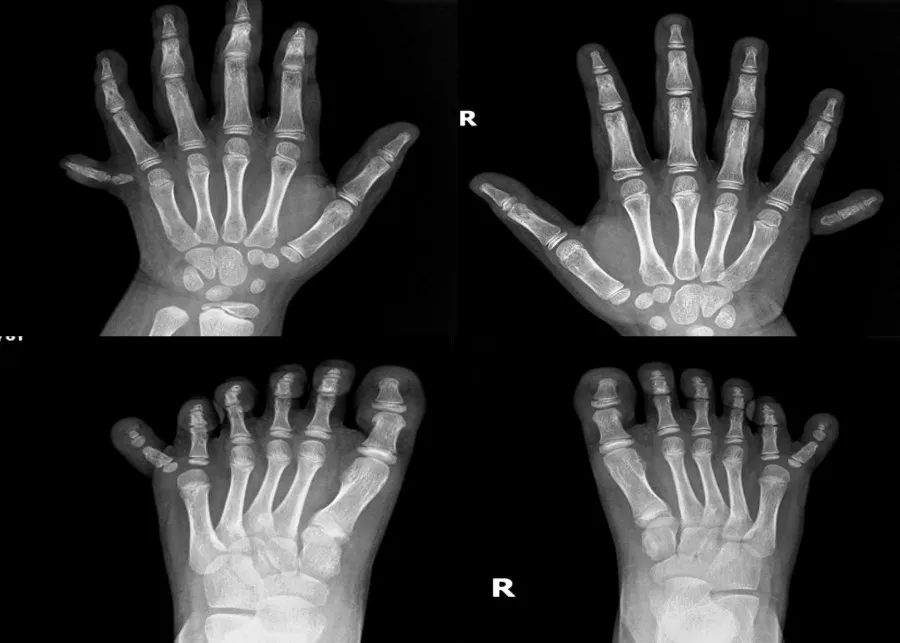

Các chi của bé gái trước và sau phẫu thuật. Ảnh: BVCC |

Sau ba năm cân nhắc, bé TL (6 tuổi) được phụ huynh đưa đến BV Gia Đình để phẫu thuật, Ca phẫu thuật kéo dài trong 3 giờ đồng hồ với hai kíp bác sĩ tiến hành song song để rút ngắn tối đa thời gian thực hiện.

Hai ngày sau phẫu thuật, hai tay bé đã có thể thực hiện các nhiệm vụ đơn giản như nắm đồ vật, không còn bị khó chịu và đau đớn...